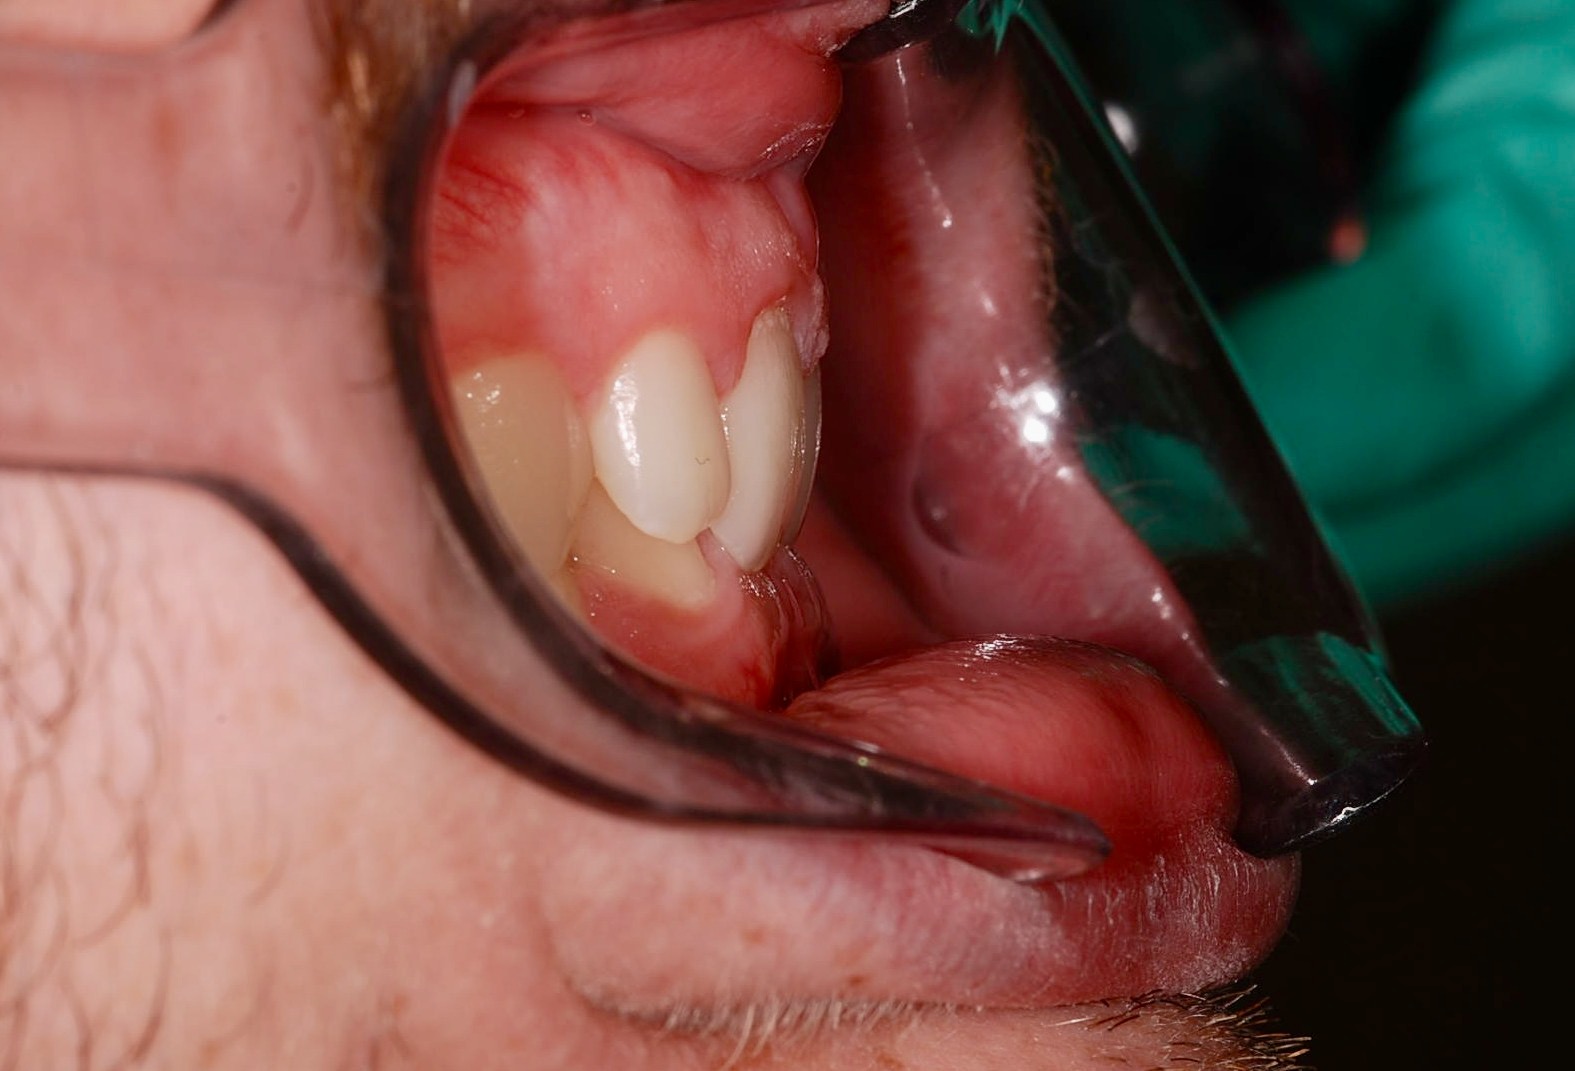

Class II subdivision malocclusions can be difficult to treat because of their asymmetric occlusal relationships. An accurate diagnosis, etiologically based when possible, is essential to perform a correct and efficient orthodontic treatment.

The aim of this article is to illustrate a case report treated with customized lingual brackets in association with a simple vestibular device.